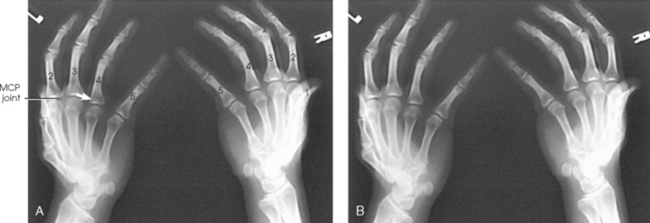

The interphalangeal (IP) articulations between the phalanges are synovial hinge type and allow only flexion and extension (Fig. 4-8). The IP joints are named by location and are differentiated as either proximal interphalangeal (PIP) or distal interphalangeal (DIP), by the digit number, and by right or left hand (e.g., the PIP articulation of the fourth digit of the left hand) (Fig. 4-9, A and B). Because the first digit has only two phalanges, the joint between the two phalanges is simply called the IP joint.

Fig. 4-8 A, Sagittal MRI of finger showing IP and MCP joints. B, Coronal MRI of hand and wrist showing same joints.

Fig. 4-9 A, Articulations of hand and wrist. B, Radiocarpal articulation formed by scaphoid, lunate, and triquetrum with radius. C, Coronal MRI of wrist showing bones and joints of wrist.

The metacarpals articulate with the phalanges at their distal ends and the carpals at their proximal ends. The metacarpophalangeal (MCP) articulations are synovial ellipsoidal joints and have the movements of flexion, extension, abduction, adduction, and circumduction. Because of the less convex and wider surface of the MCP joint of the thumb, only limited abduction and adduction are possible.